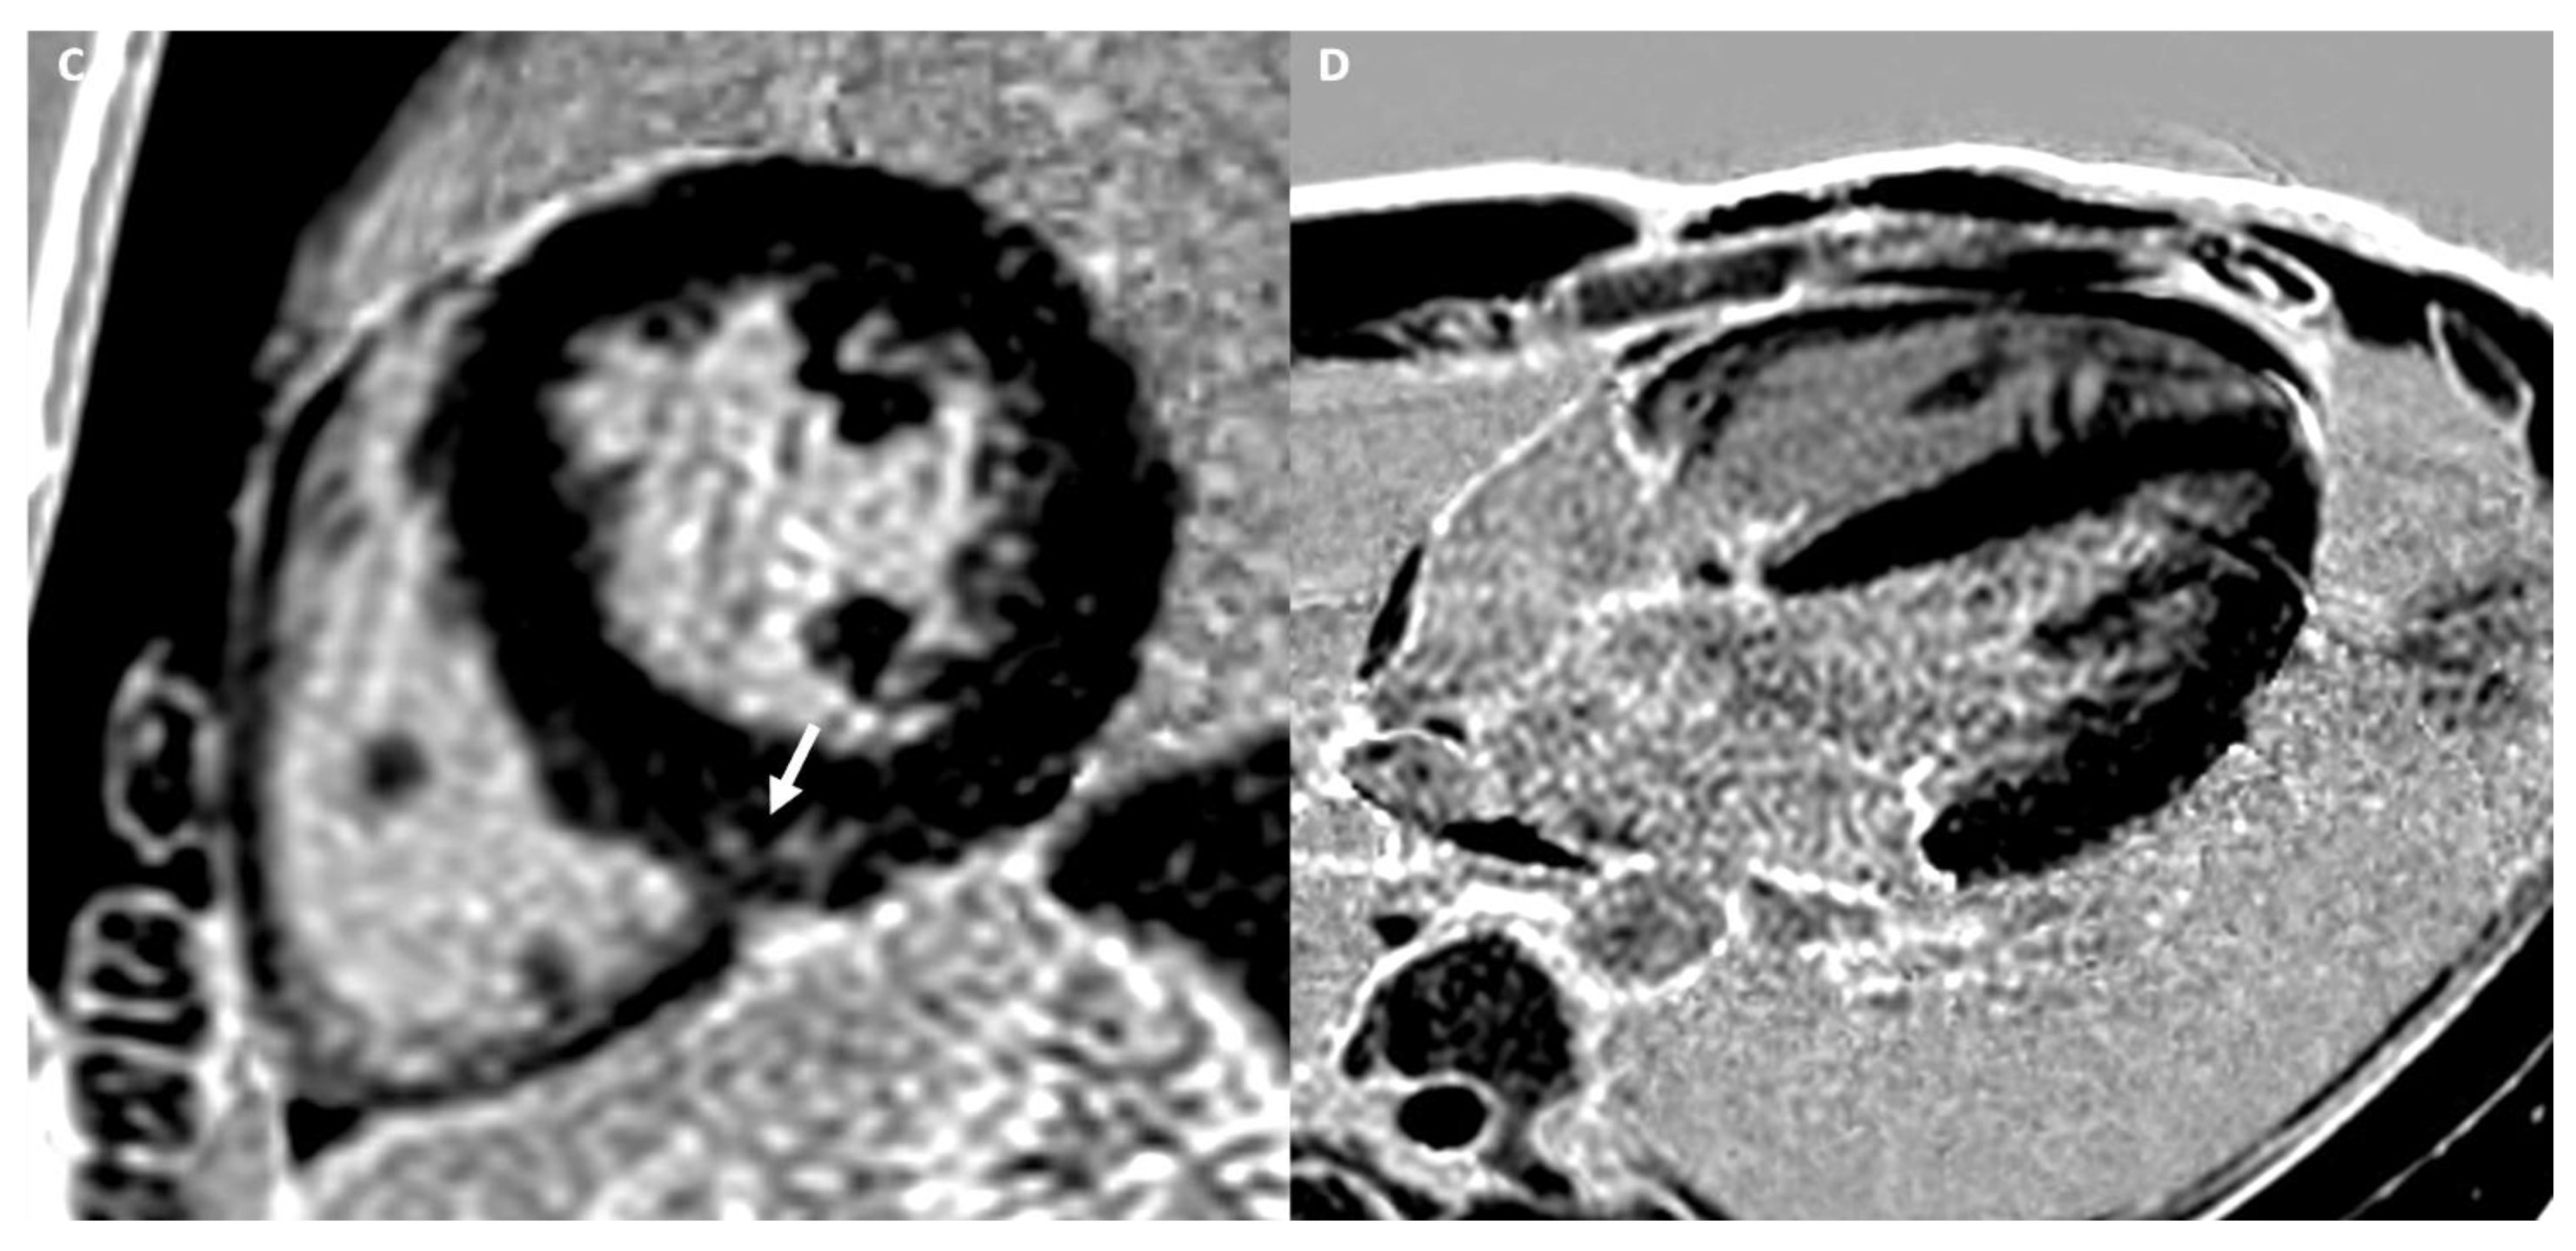

4.2.3. Cardiac Imaging: AH vs. Left Ventricular Non-Compaction

| Trabeculation | Increased | Increased | Increased | NC/C > 2.3 in two cardiac segments | - | - | - |

| LGE/LIE | |||||||

| Type | Linear | Patchy or massive | Linear | Linear | Linear | Linear | Linear or parchy |

| Layer | Mesocardial | Mesocardial | Mesocardial | Mesocardial | Subepicardial Mesocardial | Subepicardial | Subendocardial Mesocardial |

| Site | Interventricular juctions | Hypertrophic area; interventricular junctions | Septum; infero-lateral LV wall | Variable, not associated with NC area | Anterior RV wall | Infero-lateral LV wall | Circumferential; septum; lateral LV wall |